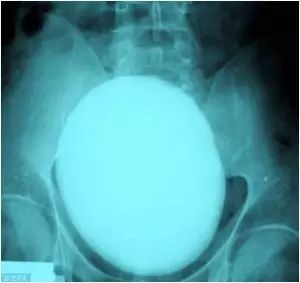

3.一个匈牙利的病人觉得自己腹部疼痛难忍。医院帮她做了X光,发现了一个7英寸的肾结石,看起来就像一个鸵鸟蛋。

一个匈牙利的病人觉得自己腹部疼痛难忍。医院帮她做了X光,发现了一个7英寸的肾结石,看起来就像一个鸵鸟蛋